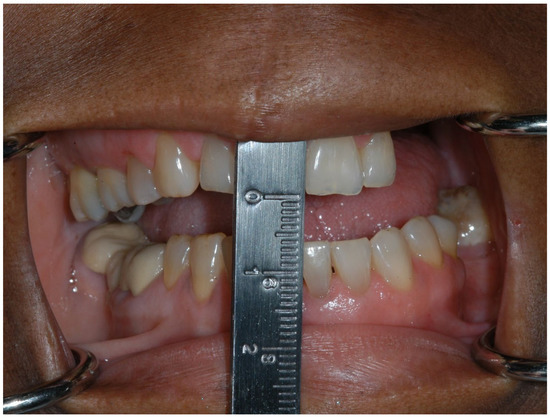

1.2. Trismus

Prevention and Management of Trismus